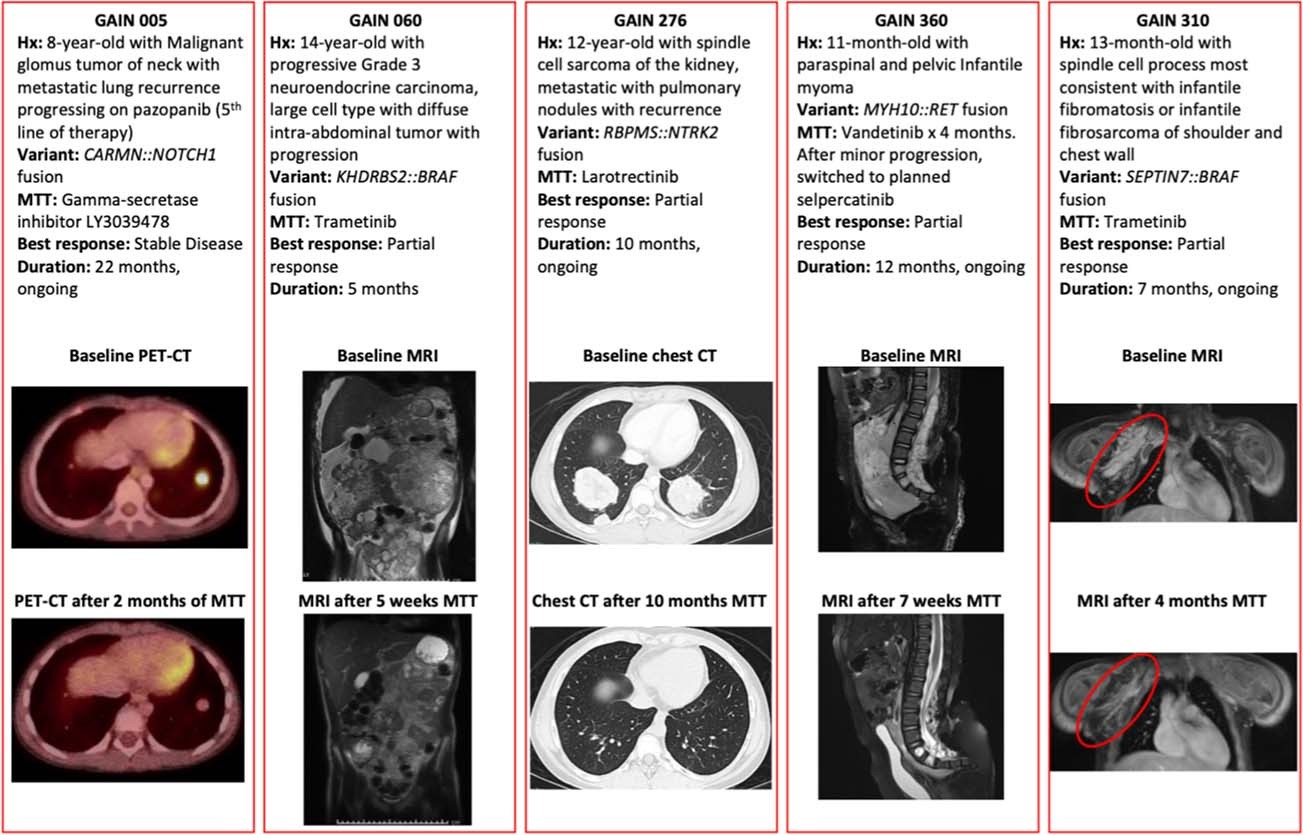

Extended Data Fig. 5: Responders to Matched Targeted Therapy.

From: Molecular profiling identifies targeted therapy opportunities in pediatric solid cancer

Details of 5 responders to matched targeted therapy. GAIN patient 317 with an ALK fusion in a medullary thyroid carcinoma also responded, with images available in the primary report (Hillier et al., 2019).